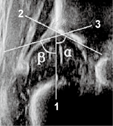

骨顶线(bony roof line):骨顶线是髂骨下肢与骨缘区的切线(图2)。有作者称为"髋臼盖线" [3,5,12,18],或"骨性顶线" [16],或"骨性髋臼骨顶线" [19,20]。骨顶线既不能穿过髂骨下肢,也不能切入骨缘区。骨顶线穿过髂骨下肢[2,3,5,6,12,18],α角就会变大;骨顶线切入骨缘区,α角就会变小。这两种情况所得到α角可重复性差。当髋关节位于临界点时,这两种测量法在不同检查者测量下会得出不同诊断。

软骨顶线(caterliage roof line):软骨顶线是骨缘与髋臼盂唇中央的连线,即由三角形髋臼盂唇中央向骨缘区内侧缘做一条切线(图2)。有作者称为"扩张线或软骨髋臼盖线" [3,5,12,18],或"髋臼软骨顶线" [19,20]。黄冠兰[11]认为软骨顶线由三角形髋臼盂唇中央与"骨缘转折点"的连线,"骨缘转折点"位于骨缘区上,在这种情况下软骨顶线势必插入骨缘区而不能过骨缘,所得到β角要比实际小。β角对于区分Ⅰa型与Ⅰb型以及Ⅱc型与D型髋关节很重要。

国内很多医生认为三条线交于一点[2,3,5,12,18],有医生将骨顶线与软骨顶线交于一点[6]。特殊情况下,当骨缘区呈锐角、骨缘接近于基线时,三条线可以看成相交于一点。一般情况下,三条测量线不相交于一点[1]。如果强调三条线相交于一点,基线会向内侧倾斜切入骨缘区,骨顶线切入骨缘区,软骨顶线也切入骨缘区,得到α角、β角就可能偏小;这个交点的确定具有主观性,不同人的测量或相同人的重复测量就不可能得到一致结果,表现为α角、β角测量结果不稳定。同样,当髋关节位于临界点时,这种测量法在不同的检查者测量或相同人的重复测量下有可能会得出不同的诊断。